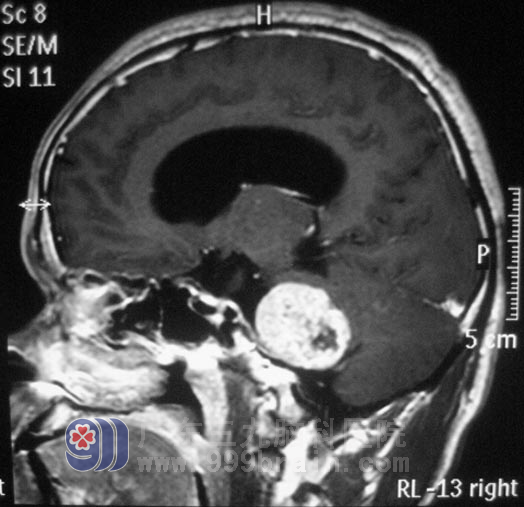

区先生,今年44岁。五年前开始出现右耳听力下降,间断头晕,呈阵发性,当地医院考虑是五官科问题,予对症治疗后症状无明显好转,且右耳听力下降不断加重。三个月前,他逐渐出现双眼视力下降,间断头晕伴有恶心感。头颅CT检查,结果提示“右侧桥小脑角区占位,约3.5cm×3.2cm,考虑听神经瘤,伴梗阻性脑积水”。

入住广东三九脑科医院综合神经外科时,区先生左侧侧鼻唇沟变浅,露齿时口角向右侧歪斜,双耳听力下降(右耳明显),闭目难立征(+),易向右侧倾倒。12月20日,由鲁明主任主刀,在全麻下行右侧乙状窦入路听神经瘤切除术。术中显微镜下见黄白色肿瘤组织,位于右侧桥小脑角区,质软,血供丰富,面神经位于肿瘤前下方,副神经、迷走神经、舌咽神经位于肿瘤后下方,神经组织形态菲薄,在显微镜下用超声刀分块切除,磨钻磨除部分内听道,切除内听道内肿瘤组织,中后组颅神经保护完好,手术顺利结束。术后病理结果为:(右侧桥小脑角)神经鞘瘤。